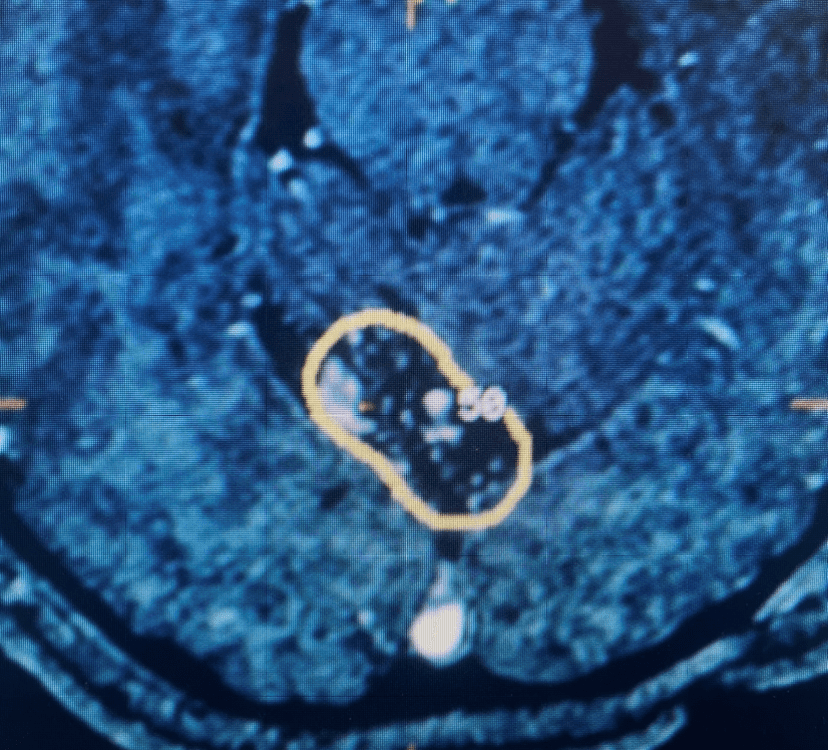

This is a 57-year-old woman with new onset memory problems and gait difficulty. MRI demonstrated a 3 cm tumor in the pineal region, most consistent with […]